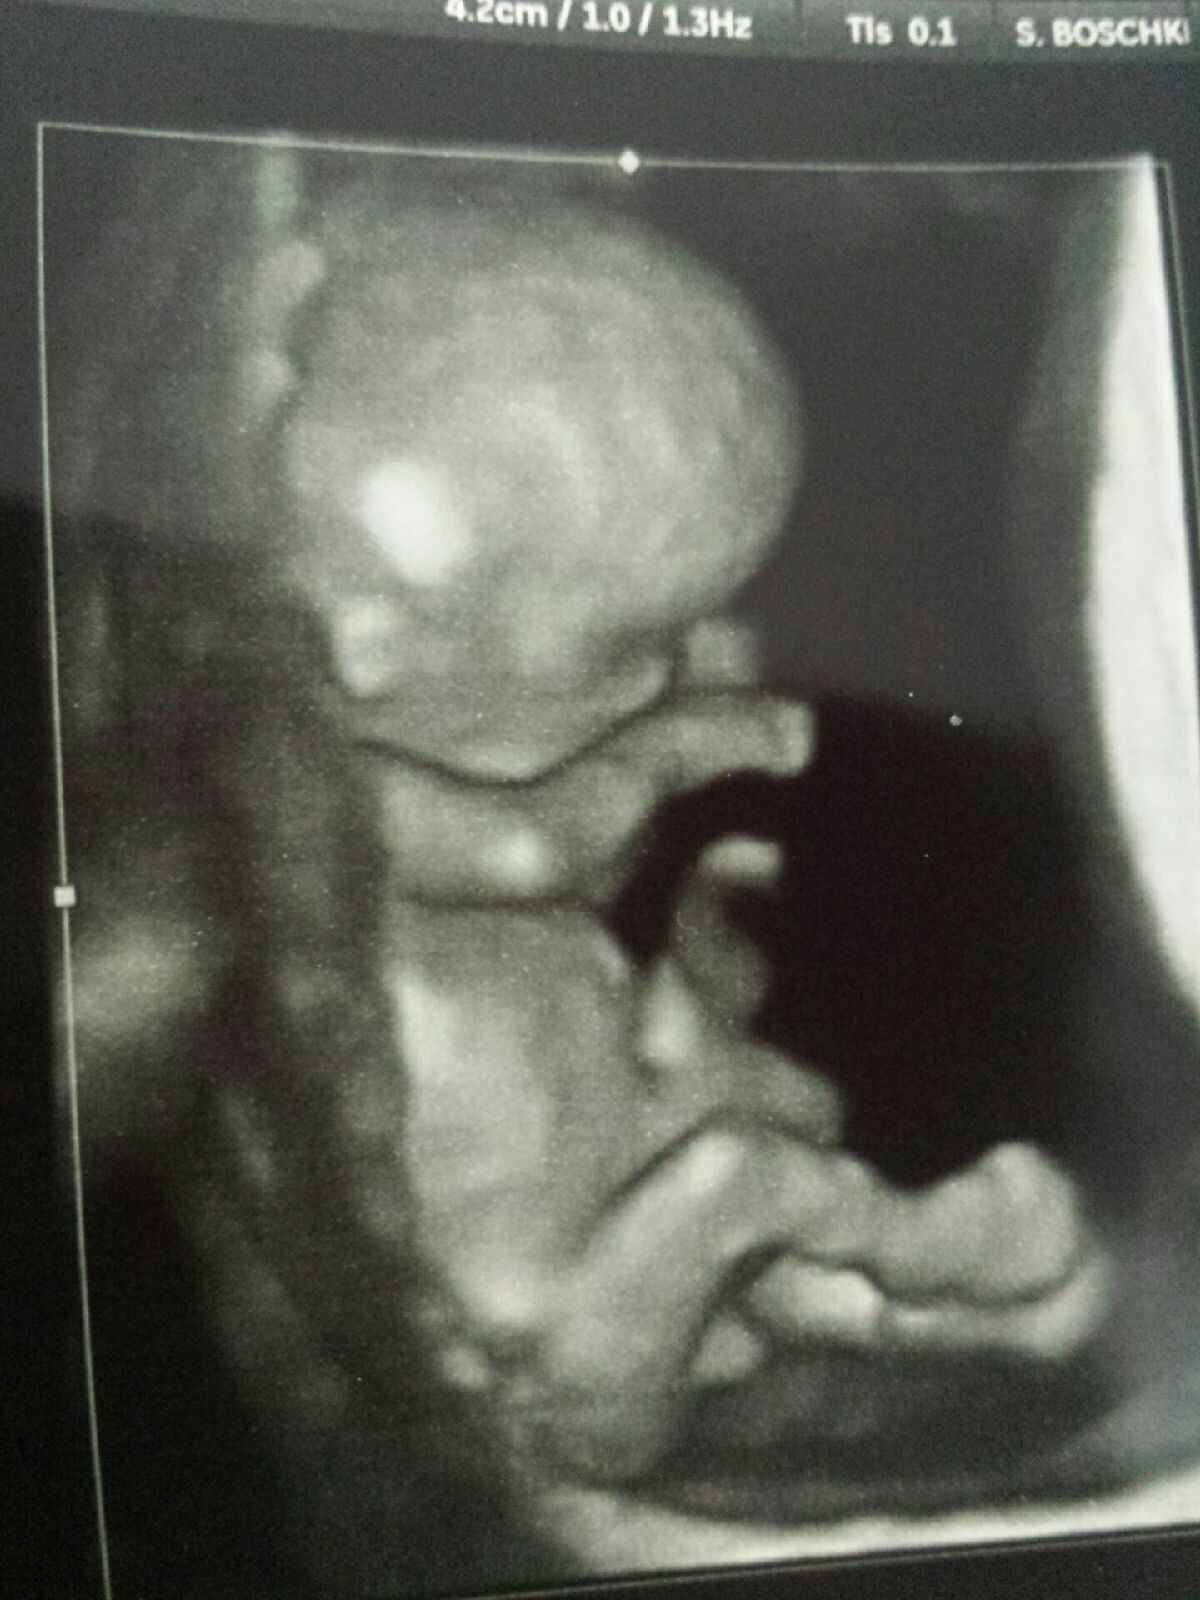

@mrscaterosales... Thank you!! My husband thinks I'm having a transformer or something! Lol! It was the coolest experience tho, you are gonna love it!! So glad he/she finally laid still enuf for a decent pic, I have like 8 others that look kinda alien:)